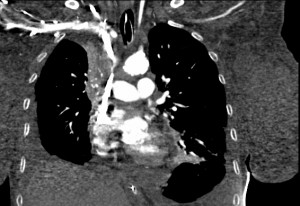

The diagnosis is usually clinical. Once clinical suspicion arises, imaging needs to be utilized. Sometimes we begin to suspect this diagnosis because of a combination of typical clinical signs and symptoms and a widened mediastinum on plain chest radiograph. However, the best imaging study for diagnosing an obstruction in the superior vena cava or compressing mass is CT with intravenous contrast. MR and PET-CT may have their value in specific cases, though. Other than the diagnosis of superior vena cava compression or thrombosis, the cause needs to be identified fully. Therefore, many times biopsy and pathological tests are needed to compliment imaging. Tissue may be obtained in various methods including from sputum, pleural fluid, mediastinoscopy or open surgical biopsy. Before intervention (see ‘treatment of superior vena cava syndrome’), venography may be needed, although it is sometimes a combined diagnostic and therapeutic intervention.

We use superior vena cava stenting in patients with SVCS secondary to malignancy as a rescue procedure in patients with severe swelling or shortness of breath. Stents may be used either as secondary, rescue, treatment when chemotherapy and or radiation have failed or as first line treatment. After successful stenting, symptoms are expected to resolve within 24-48 hours.

The durability of palliative superior vena cava stenting procedures is rather good considering the usual patient overall condition. Therefore, the superior vena cava syndrome does not usually return to bother the patient and proper treatment endeavors can be sought. However, recurrence happens in in 10-20% of patients, and then re-treatment is needed in a similar manner to the first one. Superior vena cava stents may be self-expanding or balloon expandable. There are several types of stents that are in use for treatment of superior vena cava syndrome. These include self-expanding stents and balloon-expandable stents. Choice of the proper stent depends on how tight the superior vena cava stenosis is, the length of the lesion and on vessel curvature.

Examples of stents that are being used for treatment of superior vena cava syndrome include the Palmaz balloon-expandable stent and the self-expanding Wallstent and memotherm stents. Despite relative ease of stent implantation and expected high frequency of relief of symptoms, it is important to remember that superior vena cava stenting does have (rare) complications. Stent occlusion is the most common complication of superior vena cava stenting (occurring in up to 33% of cases). This is secondary to thrombosis or tumor invasion. However, as stated before stent re-stenosis can be treated with options such as thrombolysis, thromboaspiration or re-stenting. There are other, rarer complications, such as stent misplacement, stent migration and rupture of the vena cava during insertion.